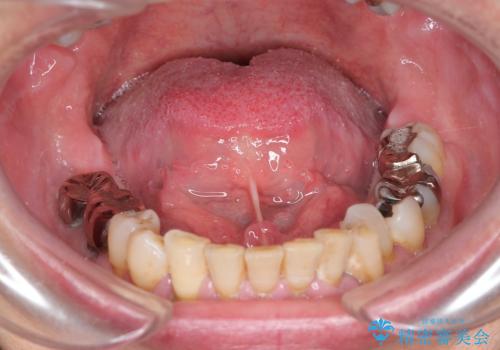

『舌小帯形成術』 ベロの動きを良くして滑舌を改善したい

- 舌の動きが制限され、滑舌を改善したい、と希望され来院されました。

舌小帯形成術を行うことで、滑舌の改善を図ります。形成術は約5分程度で終了し、1週間後に抜糸を行い治療は終了となります。

術後、舌の動きが改善され滑舌の改善を実感することができました。